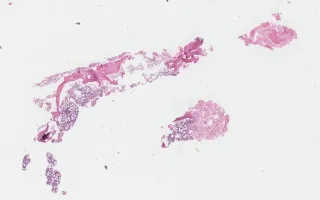

Bone marrow, Acute Undifferentiated Leukemia, H&E stain

Acute Undifferentiated Leukemia

75-year-old male with pancytopenia.

This slide shows H&E of bone marrow biopsy. See related content for peripheral blook, bone marrow aspirate, and IHC stains of bone marrow biopsies.